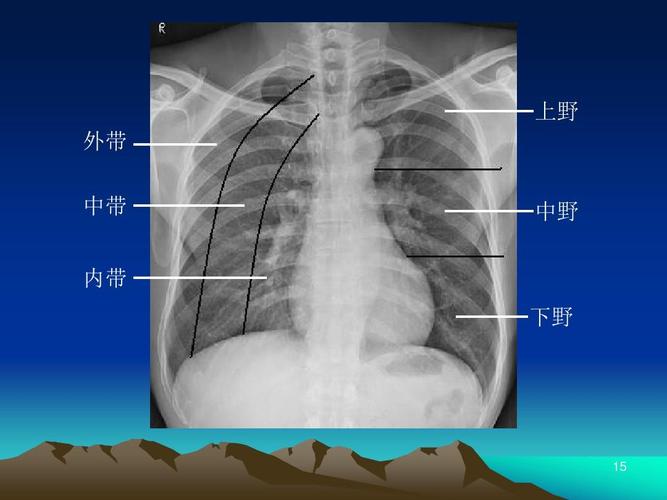

肺的三野三带划分图

胸片肺野的划分

肺野分区示意图

肺野分区

肺野